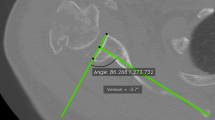

Volumetric CT scan was done with a 64-detector row CT scanner (SOMATOM Sensation 64; Siemens, Erlangen, Germany). Acquisition parameters were as follows: collimation 64 × 0.6 mm, tube current 120 mA, tube voltage 120 kV, rotation time 500 ms, and pitch 1. Reconstruction parameters were as follows: slice thickness 0.6 mm, slice increment 0.3 mm, high spatial frequency kernel (B90 for bone reconstruction), and bone window WL200 WW2000. The adopted acquisition and reconstruction protocol allowed for 0.3-mm spatial resolution of CT images. CT images were reviewed on a Volume Zoom Wizard workstation (Siemens, Erlangen, Germany) by three radiologists (>10-years of experience in musculoskeletal radiology) with the aim of measuring the glenoid surface (Fig. 4). First, the CT Pico method was used to quantify the inferior glenoid surface on volumetric CT images (slice thickening 0.6 mm) [10]. Because the CT Pico method relies on the anatomical assumption that the “bare spot” of articular glenoid surface is in the center of a circumference overlaying the inferior glenoid, oblique sagittal flat multiplanar reformatting (fMPR) was obtained to allow an “en face” view of the glenoid surface. Each observer created his or her own MPR planes for each measurement.

The landmarks of the observers, to position the circle, were the anterior and posterior margins of the equatorial region of the glenoid. The equator was angled so that it would be perpendicular to the true north–south axis of the glenoid. An electronic circumference of the circle in the region of interest (ROI) was placed on the sagittal CT glenoid surface, with particular attention to overlaying this geometric circumference on the inferior glenoid bone edge. The circle did not extend beyond the cortical bone of the inferior glenoid surface (Fig. 4). To assess intra and inter-observer agreement, the three radiologists repeated the measurements 1 month apart on each glenoid specimen [7, 13]. Overall, the three readers carried out 60 measurements using the CT Pico Method (20 for each reader, two for each scapular glenoid). Pico and laser measurements were compared to assess differences between radiological assessment and the reference standard.

The inscription of the inferior glenoid in a circle, which occurs on flat MPR images, did not correspond to the real anatomy of the glenoid surface, which, besides being curved, is difficult to compare to a circle, thus reducing the accuracy of the CT Pico method (Fig. 3c–d).

One normal glenoid specimen (a) and the model derived from laser scanning (b) are illustrated. The measurement of the glenoid surface by the CT Pico method is reported on laser (c) and CT data (d). Note as a part of the anterior glenoid is not included in the circle using the CT Pico method (arrows in c and d). The inscription of the inferior glenoid in the circle, which occurs on flat MPR images (d), could not correspond to the real anatomy of the glenoid surface, which, besides being curved, is never comparable to a circle; this obviously reduces the accuracy of the CT Pico method

Since reliability of such a method appears to be weak when considering the glenoid surface of cadaveric specimens, it is probably not accurate for measuring the amount of bone loss in cases where the glenoid is deficient (Figs. 3 and 4)